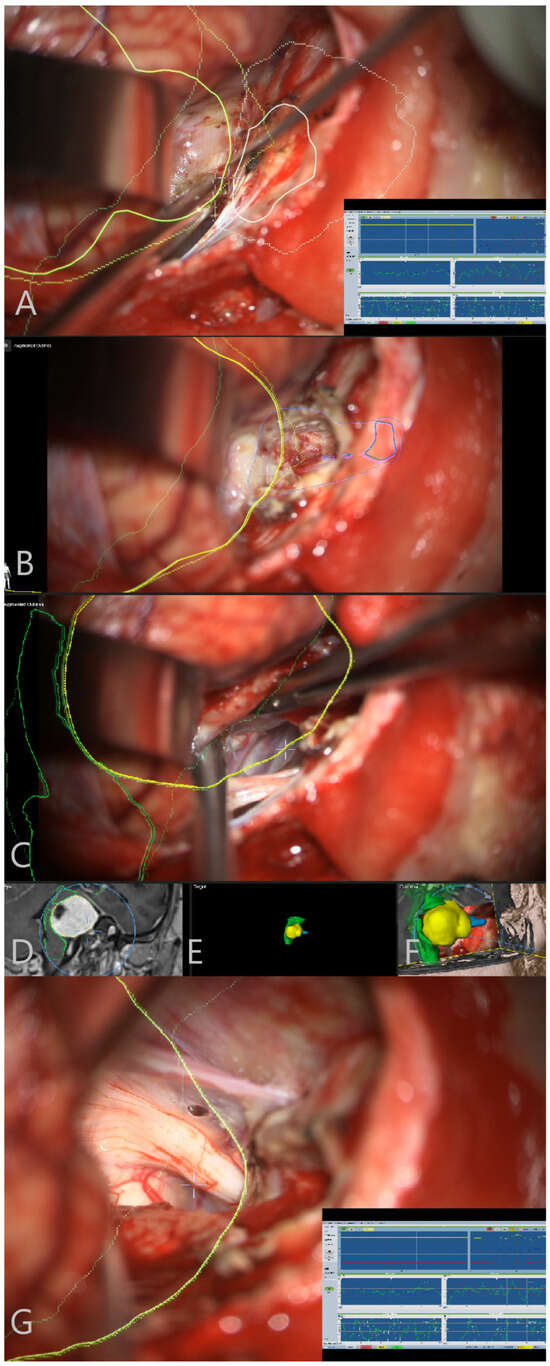

Illustrative Cases